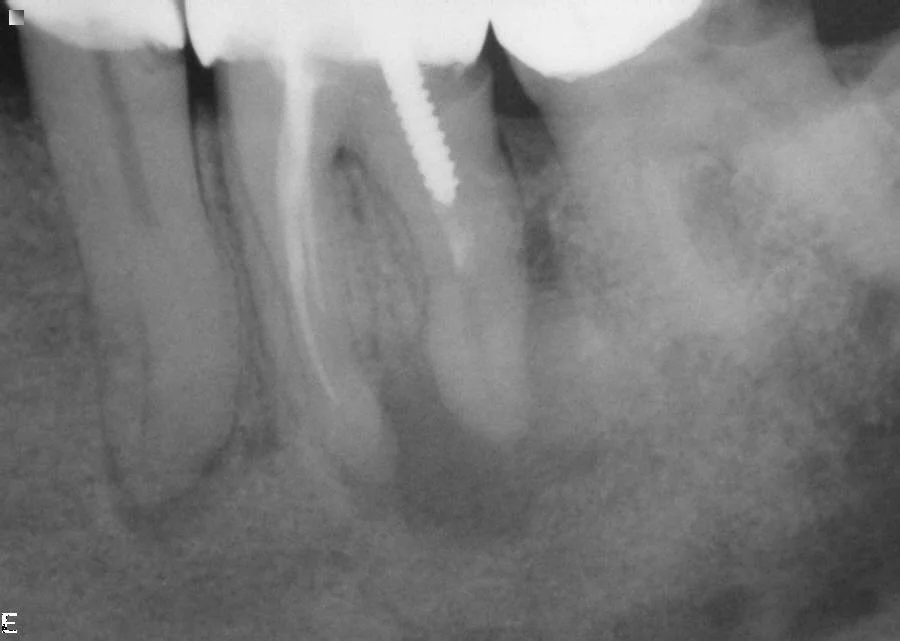

Both roots are infected and the crown is held in place with a metal screw. In addition there is decay under the crown. The options are to remove the crown and screw, re-do the root treatment, rebuild the tooth and make a new crown OR extract the tooth.

Crown and post were removed and we successfully root treated three roots and rebuilt the tooth in preparation for a new crown.